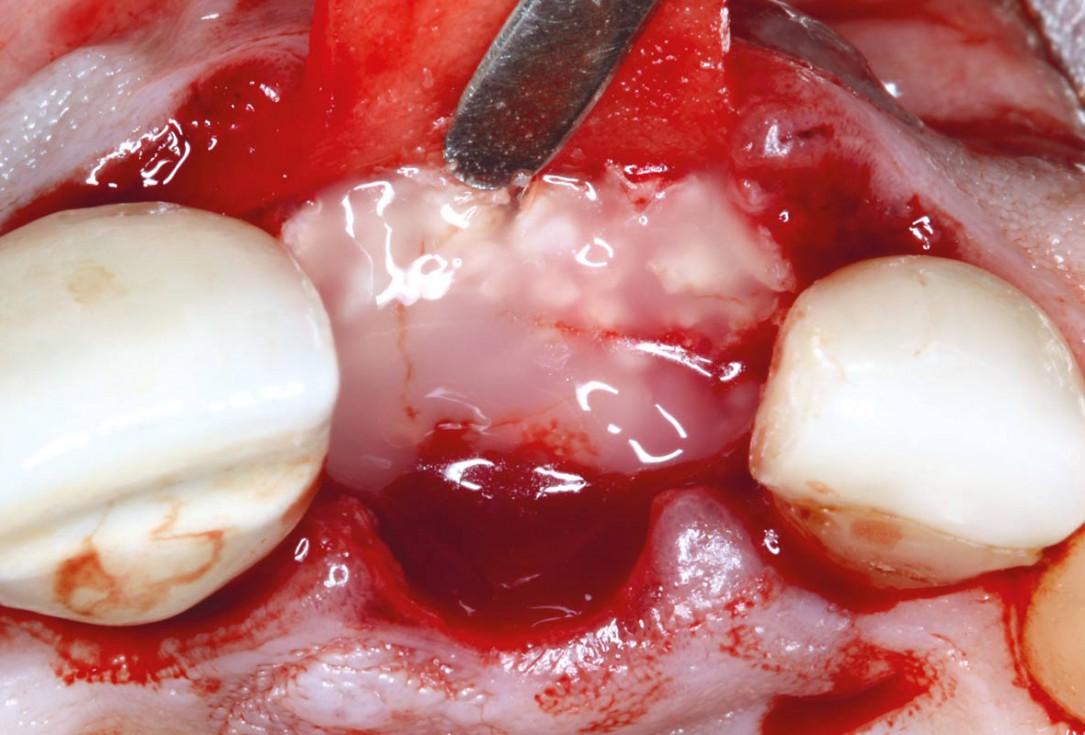

01/10 - Alveolar socket before soft and hard tissue augmentation

Socket augmentation using mucoderm®, maxgraft® and Straumann® Emdogain® - Dr. A. Puišys